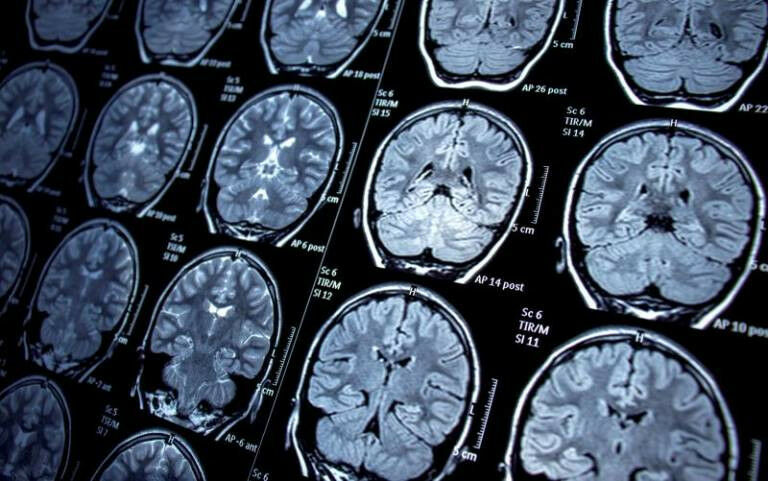

MRI scans - Researchers at the UCL Queen Square Institute of Neurology have discovered a network of connections in the brain linked to seizures in people with epilepsy. The team believe that their findings, published in Brain , will help redesign neurological operations for patients whose epilepsy can't be controlled by medication. By disconnecting certain pathways in the frontal lobe, patients may be able to enjoy long-lasting freedom from seizures. There are 500,000 people in the UK with epilepsy and 50 million people have the condition worldwide. But one in three cannot control their epilepsy with medication. For those patients where the source of epilepsy can be pinpointed, neurosurgery can be curative. However, currently only around 30% of patients remain seizure-free in the long-term in the frontal lobe.